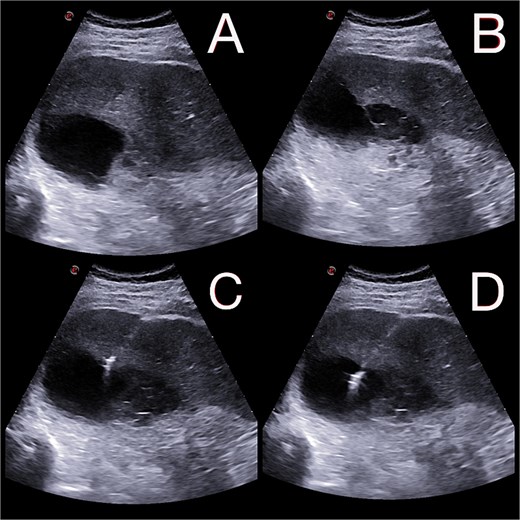

Intraoperatively, a ruptured liver abscess in segment II was found, perforating both the diaphragmatic and visceral hepatic surfaces. There was purulent discharge into the peritoneal cavity, predominantly in the upper abdomen. No gastrointestinal perforation was identified. Abdominal lavage, liver biopsy, and drainage were performed, followed by laparostomy (Fig. 1).

(A and B) Abdominal radiographs showing progression from no free gas (A) to a crescent of pneumoperitoneum beneath the right hemidiaphragm (B, arrow) within 2 hr. (C and D) Intraoperative findings of a ruptured pyogenic liver abscess in segment II, perforating both the diaphragmatic and visceral hepatic surfaces.